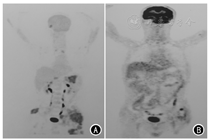

患者男,65岁,因左侧髋部及下肢疼痛1周余,于2018年7月就诊于吉林大学中日联医院。7月23日正电子发射计算机体层摄影(positron emission tomography-computed tomography, PET-CT)检查示,左侧髂骨、髋臼糖代谢增高伴骨质密度不均匀,局部骨质破坏伴软组织密度影形成,最大标准摄取值(SUVmax)为16.90。行超声引导下左侧髂骨肿物穿刺,病理诊断:不除外肿瘤性病变。先后于北京积水潭医院、北京大学肿瘤医院、北京中日友好医院病理科会诊,病理诊断:梭形细胞肿瘤组织,伴散在炎细胞浸润,符合炎症性肌纤维母细胞瘤(inflammatory myofibroblastic tumor, IMT)。免疫组化:CD20(散在+),CK(-),CD1a(-),CD34(-),CD68(+),S-100(-),CD3(散在+),Ki-67(5%),EMA(-),actin(-)。8月29日对左侧髂骨肿物行CT引导下经皮微波消融术。术后症状缓解不明显,于11月28日再次行左侧髂骨旁软组织肿物穿刺活检,病理诊断:考虑为IMT。免疫组化:CK(-),CD34(血管+),CD138(散在+),β-catenin(-),CD68(散在+),间变性淋巴瘤激酶(anaplastic lymphoma kinase, ALK)(-),Vimentin(+),Myogenin(-),Desmin(-),SMA(-),S-100(-),Ki-67(5%)。患者左髋部和下肢疼痛进行性加重,行动困难,左腰背和左髂部出现多发皮下结节。2019年3月25日于吉林省肿瘤医院行左腰背和左髂部皮下结节切除活检,病理诊断:考虑为肉瘤,倾向纤维源性。因左髂骨肿物第1次活检标本进行过脱钙处理,第2次活检标本在免疫组化检测后剩余不足,因此仅对患者转移组织标本(左腰背皮下结节)和血浆进行二代测序(next generation sequencing, NGS), 对患者转移组织标本行程序性细胞死亡配体1(programmed cell death-ligand 1, PD-L1)免疫组化检测。NGS由南京世和基因生物技术股份有限公司完成,检测平台为Illumina Hiseq/MiSeqDx,参考基因组为GRCh37/hg19。转移组织标本中检测到成纤维细胞生长因子受体(fibroblast growth factor receptor, FGFR1)、异柠檬酸脱氢酶1(isocitrate dehydrogenase 1, IDH1)、磷脂酰肌醇-3-激酶催化亚单位a基因(phosphatidylinositol-3-kinase catalytic alpha polypeptide gene, PIK3CA)和端粒酶逆转录酶基因(telomerase reverse transcriptase, TERT)突变,血浆标本中未检测到FGFR1突变,但IDH1、PIK3CA和TERT突变均检测到,并检测到ALK和RAS同源基因家族成员A(ras homolog gene family, member A, RHOA)突变,胚系突变和高度微卫星不稳定(microsatellite instability-high,MSI-H)未检测到。转移组织的肿瘤突变负荷(tumor mutation burden, TMB)为3.4个突变/Mb,血浆为4.6个突变/Mb,属低TMB。PD-L1免疫组化检测显示,转移组织肿瘤比例分数(tumor proportion score, TPS)为80%(图1)。4月4日查PET-CT示,右眼眶内直肌下方和内直肌可见软组织影,CT值31 HU,糖代谢增高(SUVmax=4.8),大小为2.1 cm;右第二肋间可见软组织影,CT值32 HU,糖代谢增高(SUVmax=4.7);胃周可见散在多发肿大淋巴结,较大短径约1.1 cm,糖代谢增高(SUVmax=5.2);腹腔可见散在多发肿大淋巴结影,部分融合成团,较大轴位约4.9 cm×3.8 cm, 糖代谢增高(SUVmax=6.4);腹膜后区(十二指肠降部、脾周等)见多发肿大淋巴结,较大短径约0.7 cm,糖代谢增高(SUVmax=4.6);左侧盆壁可见软组织影,周围肌(臀大肌、臀中肌、臀小肌、骨直肌、缝匠肌、闭孔内肌)内组织肿胀,边缘模糊,较大轴位约8.0 cm×12.9 cm,糖代谢增高(SUVmax=10.0);两侧髂骨、骶骨、左髋臼可见骨质破坏;右膝关节可见多发软组织影,糖代谢增高(SUVmax=10.0);左背阔肌、右臀大肌、右小腿肌内见软组织影,糖代谢增高(SUVmax=6.4);皮下组织散在多个软组织影,糖代谢增高(SUVmax=1.7,图2A),疾病明显进展。4月5日于我院开始给予帕博利珠单抗+安罗替尼联合治疗。具体方法:帕博利珠单抗200 mg,第1天;安罗替尼12 mg,第1~14天;21 d为1个周期。每月给予唑来膦酸4 mg。治疗2个周期后,患者左髋部和下肢疼痛明显减轻,可以行走,皮下结节消失。5月15日查PET-CT示,胃周、腹腔内、腹膜后淋巴结较前明显缩小,多消失,糖代谢较前减低(SUVmax=2.2);左侧盆壁软组织影较前明显缩小,糖代谢较前减低(SUVmax=2.8);两侧髂骨、骶骨、左髋臼可见骨质破坏同前,糖代谢较前减低(SUVmax=2.0);左背阔肌、右臀大肌内软组织影较前明显缩小,界限模糊,糖代谢无异常;右眼眶内和皮下组织未再见到糖代谢增高病灶(图2B)。疗效评定为部分缓解。截至目前,患者已完成10个周期抗PD1单抗联合安罗替尼治疗,耐受性良好,未出现明显不良反应,生活质量明显改善。